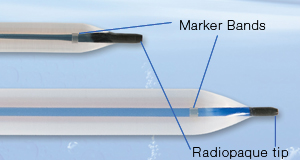

All EZDilate Balloon Dilators have a fully radiopaque tip as well as two radiopaque marker bands within the balloons to signify the distal and proximal ends of maximum dilation.

These navigation aids provide assurance of precise visualization that the device is in the desired location prior to inflation.

Radiopaque Tips